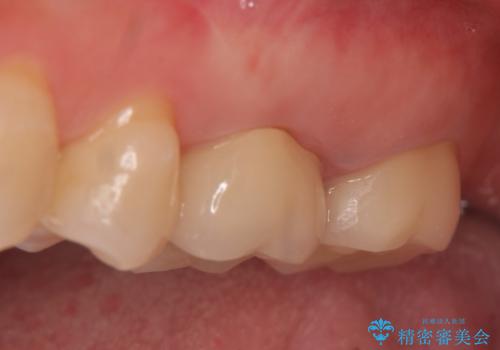

30代女性 ミゼラブルな前歯の陥没を再生する③完成へ

- 他院にて前歯を抜歯され、その後の組織の吸収によりシビアな欠損を伴う状態であった

→2度の手術により失われた骨・および軟組織の再生を図り、最終的にセラミックにて修復を終えた

完成

骨造成と2次的な結合組織の付着により

・歯牙を支持する歯槽骨の回復

・浅いポケットの獲得

・最低限の審美性の回復

が達成された。

被せものの種類:ジルコニアオールセラミック スタンダード